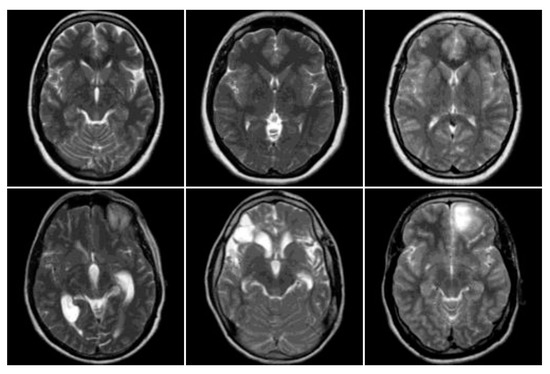

3.1. Data Collection

3.2. MRI Brain Scan Preprocessing